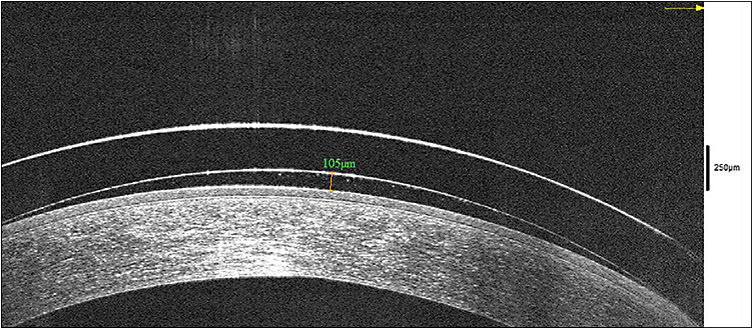

Apical clearance is important with hybrid lenses; a 100-micron clearance at dispensing (Figures 4 and 5) is recommended, as the lens may settle 30 to 60 microns. Lenses that become tight and uncomfortable after two to three hours have too much vault.